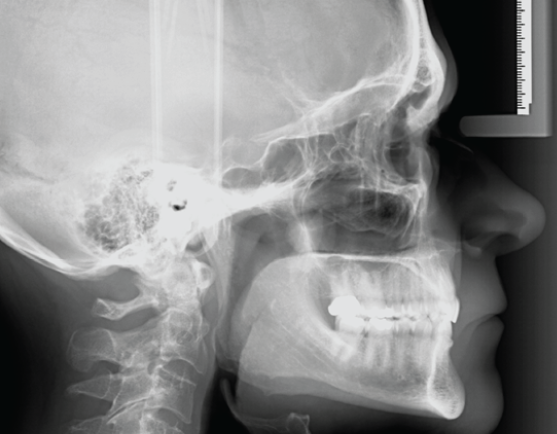

Along with the ability to transform from 2D Panoramics to Cephalometrics to 3D, the GXDP-700 Series gives clinicians dependable image capture of a wide variety of radiographs. These images are valuable for diagnosis and treatment planning of caries, root investigation, orthodontics, implants, and other surgical procedures, as well as patient education.

• Cephalometrics to facilitate analysis and the evaluation of treatment and growth changes

Ceph - Single Or Dual Sensor Solutions

With the 2D cephalometric upgrade, Gendex offers even more options. Choose a single sensor to move between panoramic and ceph to maximize your investment, or choose two sensors to increase efficiency in your workflow.